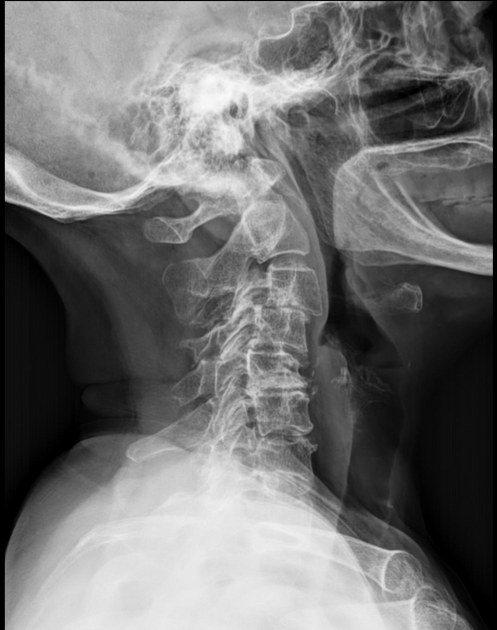

hangman’s fx

fx of anterior arch/pedicles of C2 w/ or w/o subluxation of C2 on C3, occurs w/ extreme hyperextension

teardrop fx

comminuted vertebral body w/ triangular fragments extending from body; caused by compression & hyperflexion of c-spine, best demoed on lateral or CT